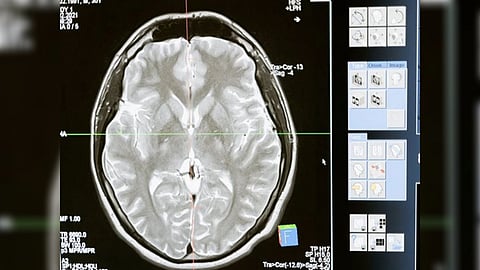

UPPSALA [Sweden]: An artificial blood-brain barrier model that has been constructed by researchers at Uppsala University is quick and accurate, and it may be used to assess how well antibody-based treatments can reach the brain.

However, the blood-brain barrier (BBB) provides a significant hurdle when trying to deliver biologics to areas of the brain to stop these large molecules causing disease.